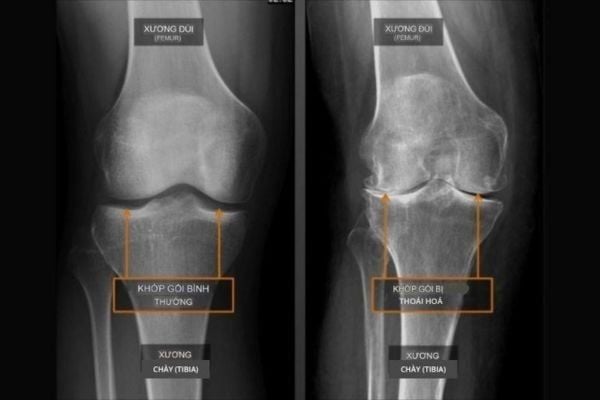

Thoái hóa khớp gối là quá trình thoái hóa xảy ra khi lớp sụn bao phủ đầu xương bị mòn, khiến hai đầu xương cọ xát trực tiếp vào nhau. Bạn có thể từng nghe bác sĩ mô tả tình trạng này là “chạm xương” (bone-on-bone). Khi đó, người bệnh thường bị đau và hình thành gai xương (osteophyte), làm cho bệnh nặng hơn.

Hình X-quang của một khớp gối bình thường (bên trái) và khớp gối bị thoái hóa (bên phải) cho thấy khoảng trống giữa xương đùi và xương chày biến mất hoàn toàn, thể hiện mức độ thoái hóa nặng.

Ở khớp gối, điều này có nghĩa là lớp sụn khớp giữa xương chày (ống chân) và xương đùi (đùi) đã bị mòn. Sụn bị tổn thương rất khó tự tái tạo, và nếu không được can thiệp kịp thời, tình trạng thoái hóa sẽ tiếp tục tiến triển theo thời gian.